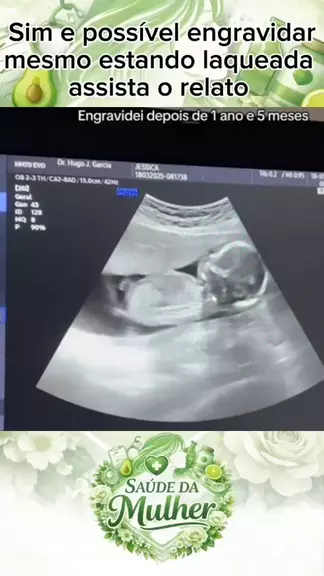

Saúde da mulher💚

mulher egravida laqueada #gravidinha #educação #Saúde